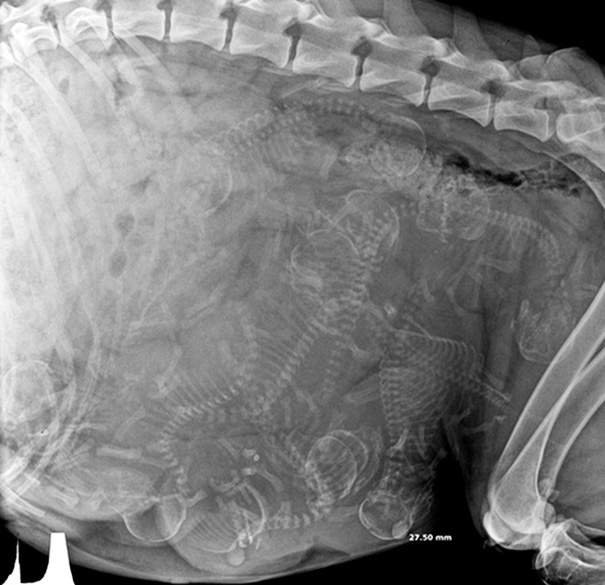

▼肚子裡滿滿的貓咪寶寶

圖片來自:boredpanda